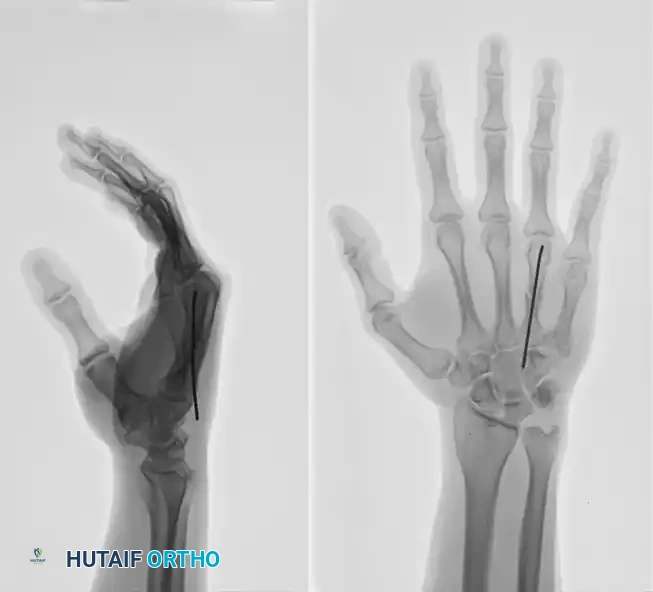

This technique is equally effective for mid-shaft fractures, as demonstrated in the fourth metacarpal example below:

FIGURE 67-37A: Preoperative AP radiograph of a fourth metacarpal shaft fracture.

FIGURE 67-37B: Preoperative lateral radiograph of the fourth metacarpal fracture.

FIGURE 67-37C: Postoperative AP radiograph showing intramedullary fixation with a Kirschner wire.

FIGURE 67-37D: Postoperative lateral radiograph confirming anatomic restoration.